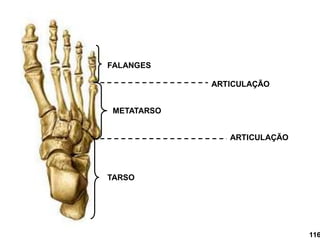

TARSO

METATARSO

FALANGES

ARTICULAÇÃO

116

Articulação Tarso

Metatarseana

Articulação Metatarso Falangeana.

Articulação Inter Falangeana.